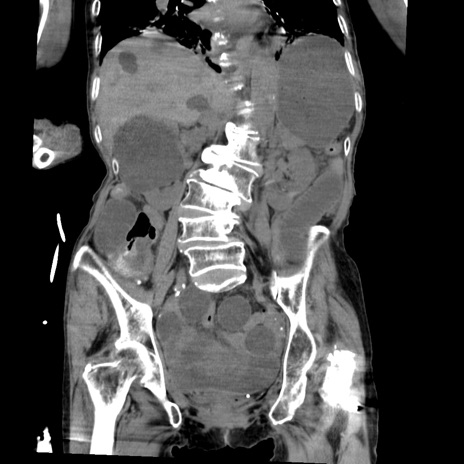

症例27(冠状断像)

【症例】80歳代女性

【主訴】嘔吐、腹痛

【現病歴】数時間前より嘔吐あり。心窩部痛出現し、徐々に右下腹痛あり。その後も数回嘔吐あり救急搬送となる。

【既往歴】左大腿骨頚部骨折手術

【身体所見】腹部は膨隆しているが軟らかく圧痛なし。腸雑音はやや亢進。

【データ】WBC 12000、CRP 19.05